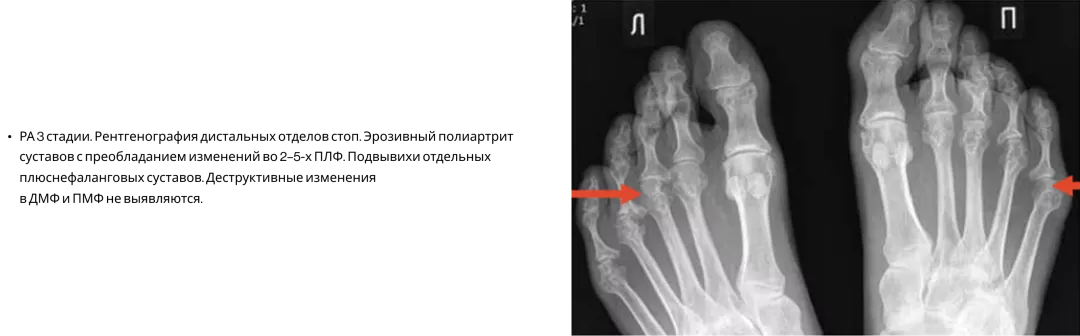

Ревматоидный артрит17

На практике ПсА часто путают с ревматоидным артритом, поскольку при обоих заболеваниях могут поражаться мелкие суставы кистей, характерны костные эрозии. В то же время для РА помимо характерных клинических симптомов есть ряд рентгенологических признаков7.

Image

Frame 24062090.png